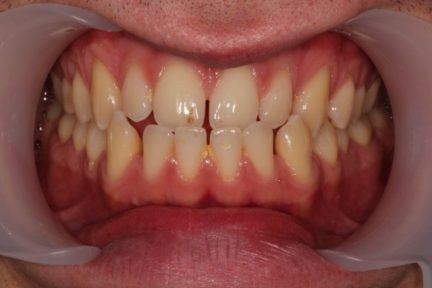

- Relation de classe I obtenue

- Guidage fonctionnel des canines des deux côtés

- Articulé antérieur corrigé

- Forme de l'arcade améliorée

- La ligne de sourire esthétique a été obtenue

- Des arcades harmoniques ont été réalisées

État final